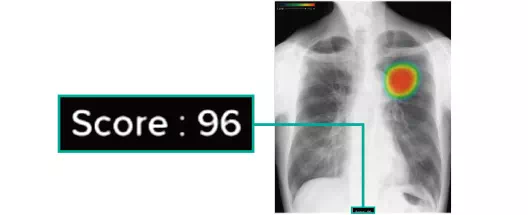

ヒートマップ表示機能

AIが異常の可能性がある領域を自動解析し、確信度に応じた表示を行います。確信度のスコアは0~100の範囲で設定され、画像上では色分けされたヒートマップとして示されます。

スコア表示機能

0~100の範囲で確信度スコアの最大値が数値として表示されます。